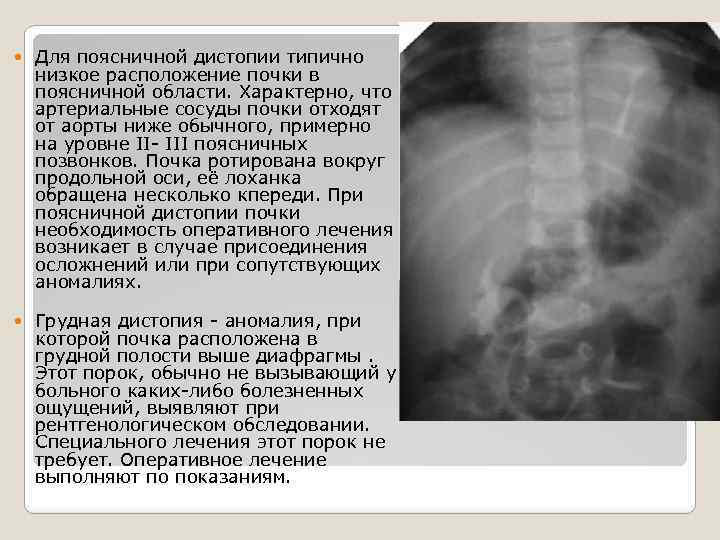

Для поясничной дистопии типично низкое расположение почки в поясничной области. Характерно, что артериальные сосуды почки отходят от аорты ниже обычного, примерно на уровне II- III поясничных позвонков. Почка ротирована вокруг продольной оси, её лоханка обращена несколько кпереди. При поясничной дистопии почки необходимость оперативного лечения возникает в случае присоединения осложнений или при сопутствующих аномалиях. Грудная дистопия - аномалия, при которой почка расположена в грудной полости выше диафрагмы. Этот порок, обычно не вызывающий у больного каких-либо болезненных ощущений, выявляют при рентгенологическом обследовании. Специального лечения этот порок не требует. Оперативное лечение выполняют по показаниям.

Для поясничной дистопии типично низкое расположение почки в поясничной области. Характерно, что артериальные сосуды почки отходят от аорты ниже обычного, примерно на уровне II- III поясничных позвонков. Почка ротирована вокруг продольной оси, её лоханка обращена несколько кпереди. При поясничной дистопии почки необходимость оперативного лечения возникает в случае присоединения осложнений или при сопутствующих аномалиях. Грудная дистопия - аномалия, при которой почка расположена в грудной полости выше диафрагмы. Этот порок, обычно не вызывающий у больного каких-либо болезненных ощущений, выявляют при рентгенологическом обследовании. Специального лечения этот порок не требует. Оперативное лечение выполняют по показаниям.